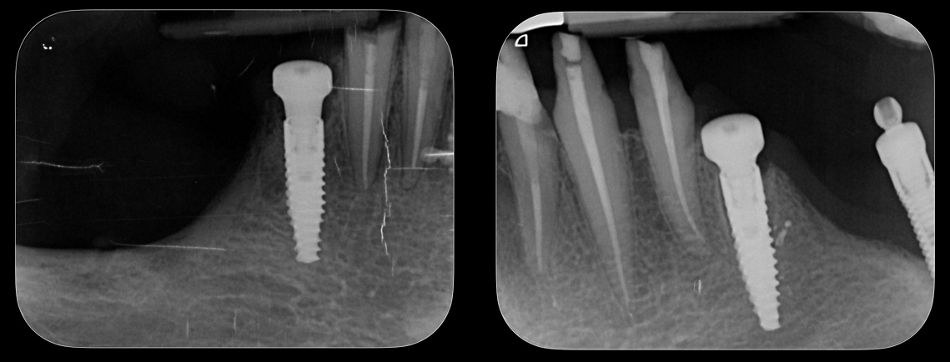

The patient returned for a follow-up three months after the placement and healing of the upper and lower implants. Examination showed healthy surrounding tissues, osseointegrated implants, and no signs of inflammation or complications. X-ray images taken at this stage confirm the quality of osseointegration in the upper and lower jaws (Fig. 50).

Fig. 50.

X-rays taken at this stage showed the precise positioning of Novaloc® abutments (Fig. 56).